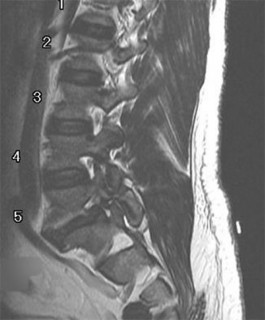

A 35-year-old male construction worker falls 10 feet from scaffolding. He complains of moderate low back pain but has full strength and normal sensation in his lower extremities.

CT imaging shows an L1 burst fracture with 40% loss of anterior vertebral body height and 50% retropulsion into the spinal canal. MRI confirms that the posterior ligamentous complex (PLC) is intact. Based on the Thoracolumbar Injury Classification and Severity (TLICS) score, what is the appropriate score and recommended management?